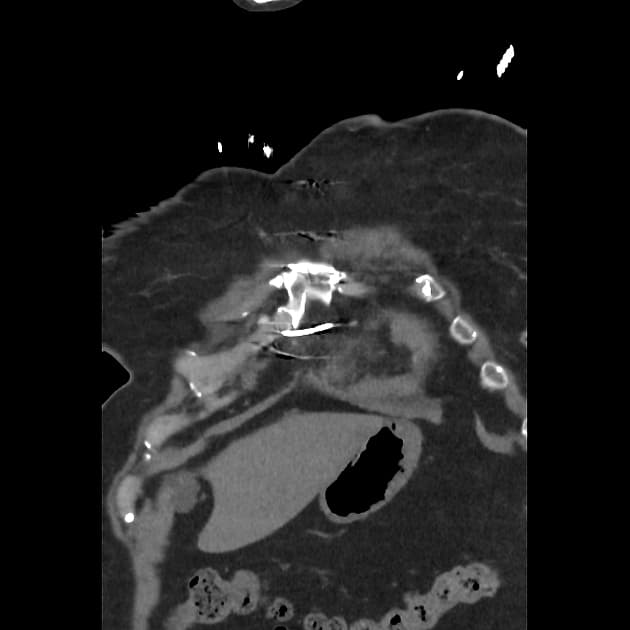

Tim

- Thấy hình ảnh phì đại cơ tim rõ rệt ở thành bên trái thất trái, với sự dày cơ tâm thất đáng kể tại đỉnh tim và hẹp đáng kể trong thì tâm thu.

Bệnh cơ tim phì đại đỉnh không tắc nghẽn (apical non-obstructive hypertrophic cardiomyopathy - Yamaguchi hypertrophy)

Bệnh cơ tim phì đại đỉnh không tắc nghẽn, còn gọi là hội chứng Yamaguchi, là một dạng biến thể hình thái của bệnh cơ tim phì đại, chủ yếu ảnh hưởng đến đỉnh thất trái mà không có tắc nghẽn đoạn ra thất trái. Bệnh lần đầu được mô tả ở Nhật Bản và phổ biến hơn ở các quần thể châu Á. Các phương tiện hình ảnh như siêu âm tim và cộng hưởng từ tim cho thấy hình ảnh dày thành đỉnh rõ rệt, thường có hình dạng giống 'cái xẻng' ở thất trái trong thì tâm trương. Mặc dù không tắc nghẽn, bệnh nhân vẫn có thể gặp các triệu chứng như đau ngực, khó thở hoặc rối loạn nhịp do rối loạn chức năng tâm trương hoặc thiếu máu vi mạch. Dấu hiệu điện tâm đồ đặc trưng là sóng T âm lớn ở các chuyển đạo trước tim giúp phân biệt với các nguyên nhân khác gây phì đại đỉnh hoặc bệnh tim thiếu máu cục bộ. Tiên lượng dài hạn thường thuận lợi, nhưng nguy cơ đột tử do tim, dù hiếm, vẫn cần được theo dõi.